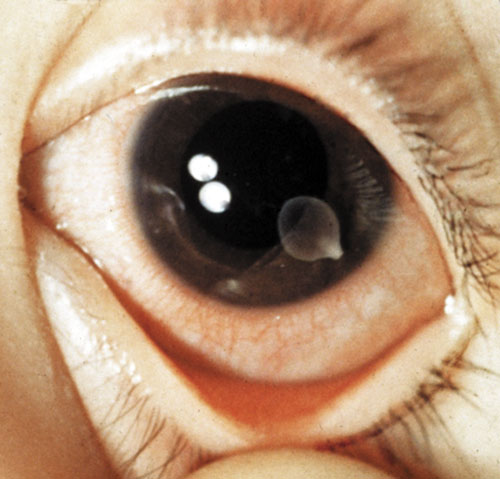

People accidentally ingest immature worms by eating raw or undercooked pork. Once the worms pass into the intestines, they latch onto the intestinal walls with suckers and hooks and begin to grow—and grow. The pork tapeworm shown here, Taenia solium, can grow as long as 20 feet (six meters). Often, people don't even know they have tapeworm until they see the worms—or pieces of them in their stool. If a person ingests the tapeworm eggs (by, for example, drinking water contaminated by egg-laden human feces), the eggs hatch into larvae the stomach and travel into the small intestine. From there, they may enter the bloodstream and migrate to the muscles, eyes or brain, where they can cause seizures, headaches and potentially fatal brain swelling.